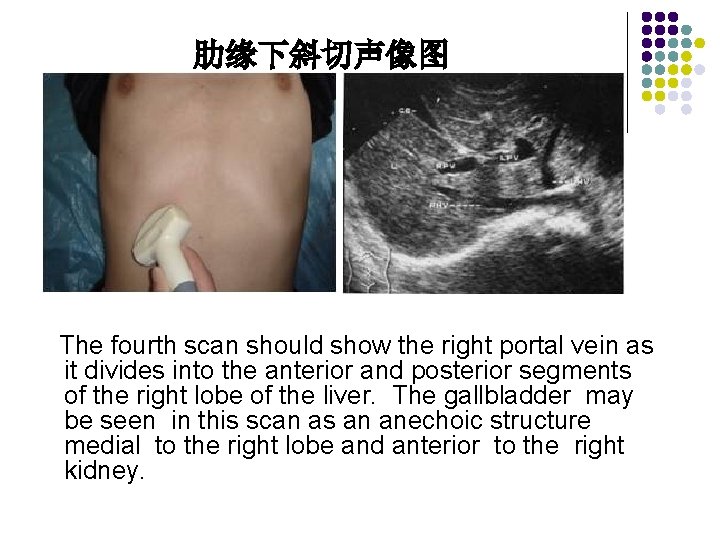

Transverse Scan Plane l Scan Ⅳ The fourth scan should show the right portal vein as it divides into the anterior and posterior segments of the right lobe of the liver. The gallbladder may be seen in this scan as an anechoic structure medial to the right lobe and anterior to the right kidney.

肋缘下斜切声像图 The fourth scan should show the right portal vein as it divides into the anterior and posterior segments of the right lobe of the liver. The gallbladder may be seen in this scan as an anechoic structure medial to the right lobe and anterior to the right kidney.